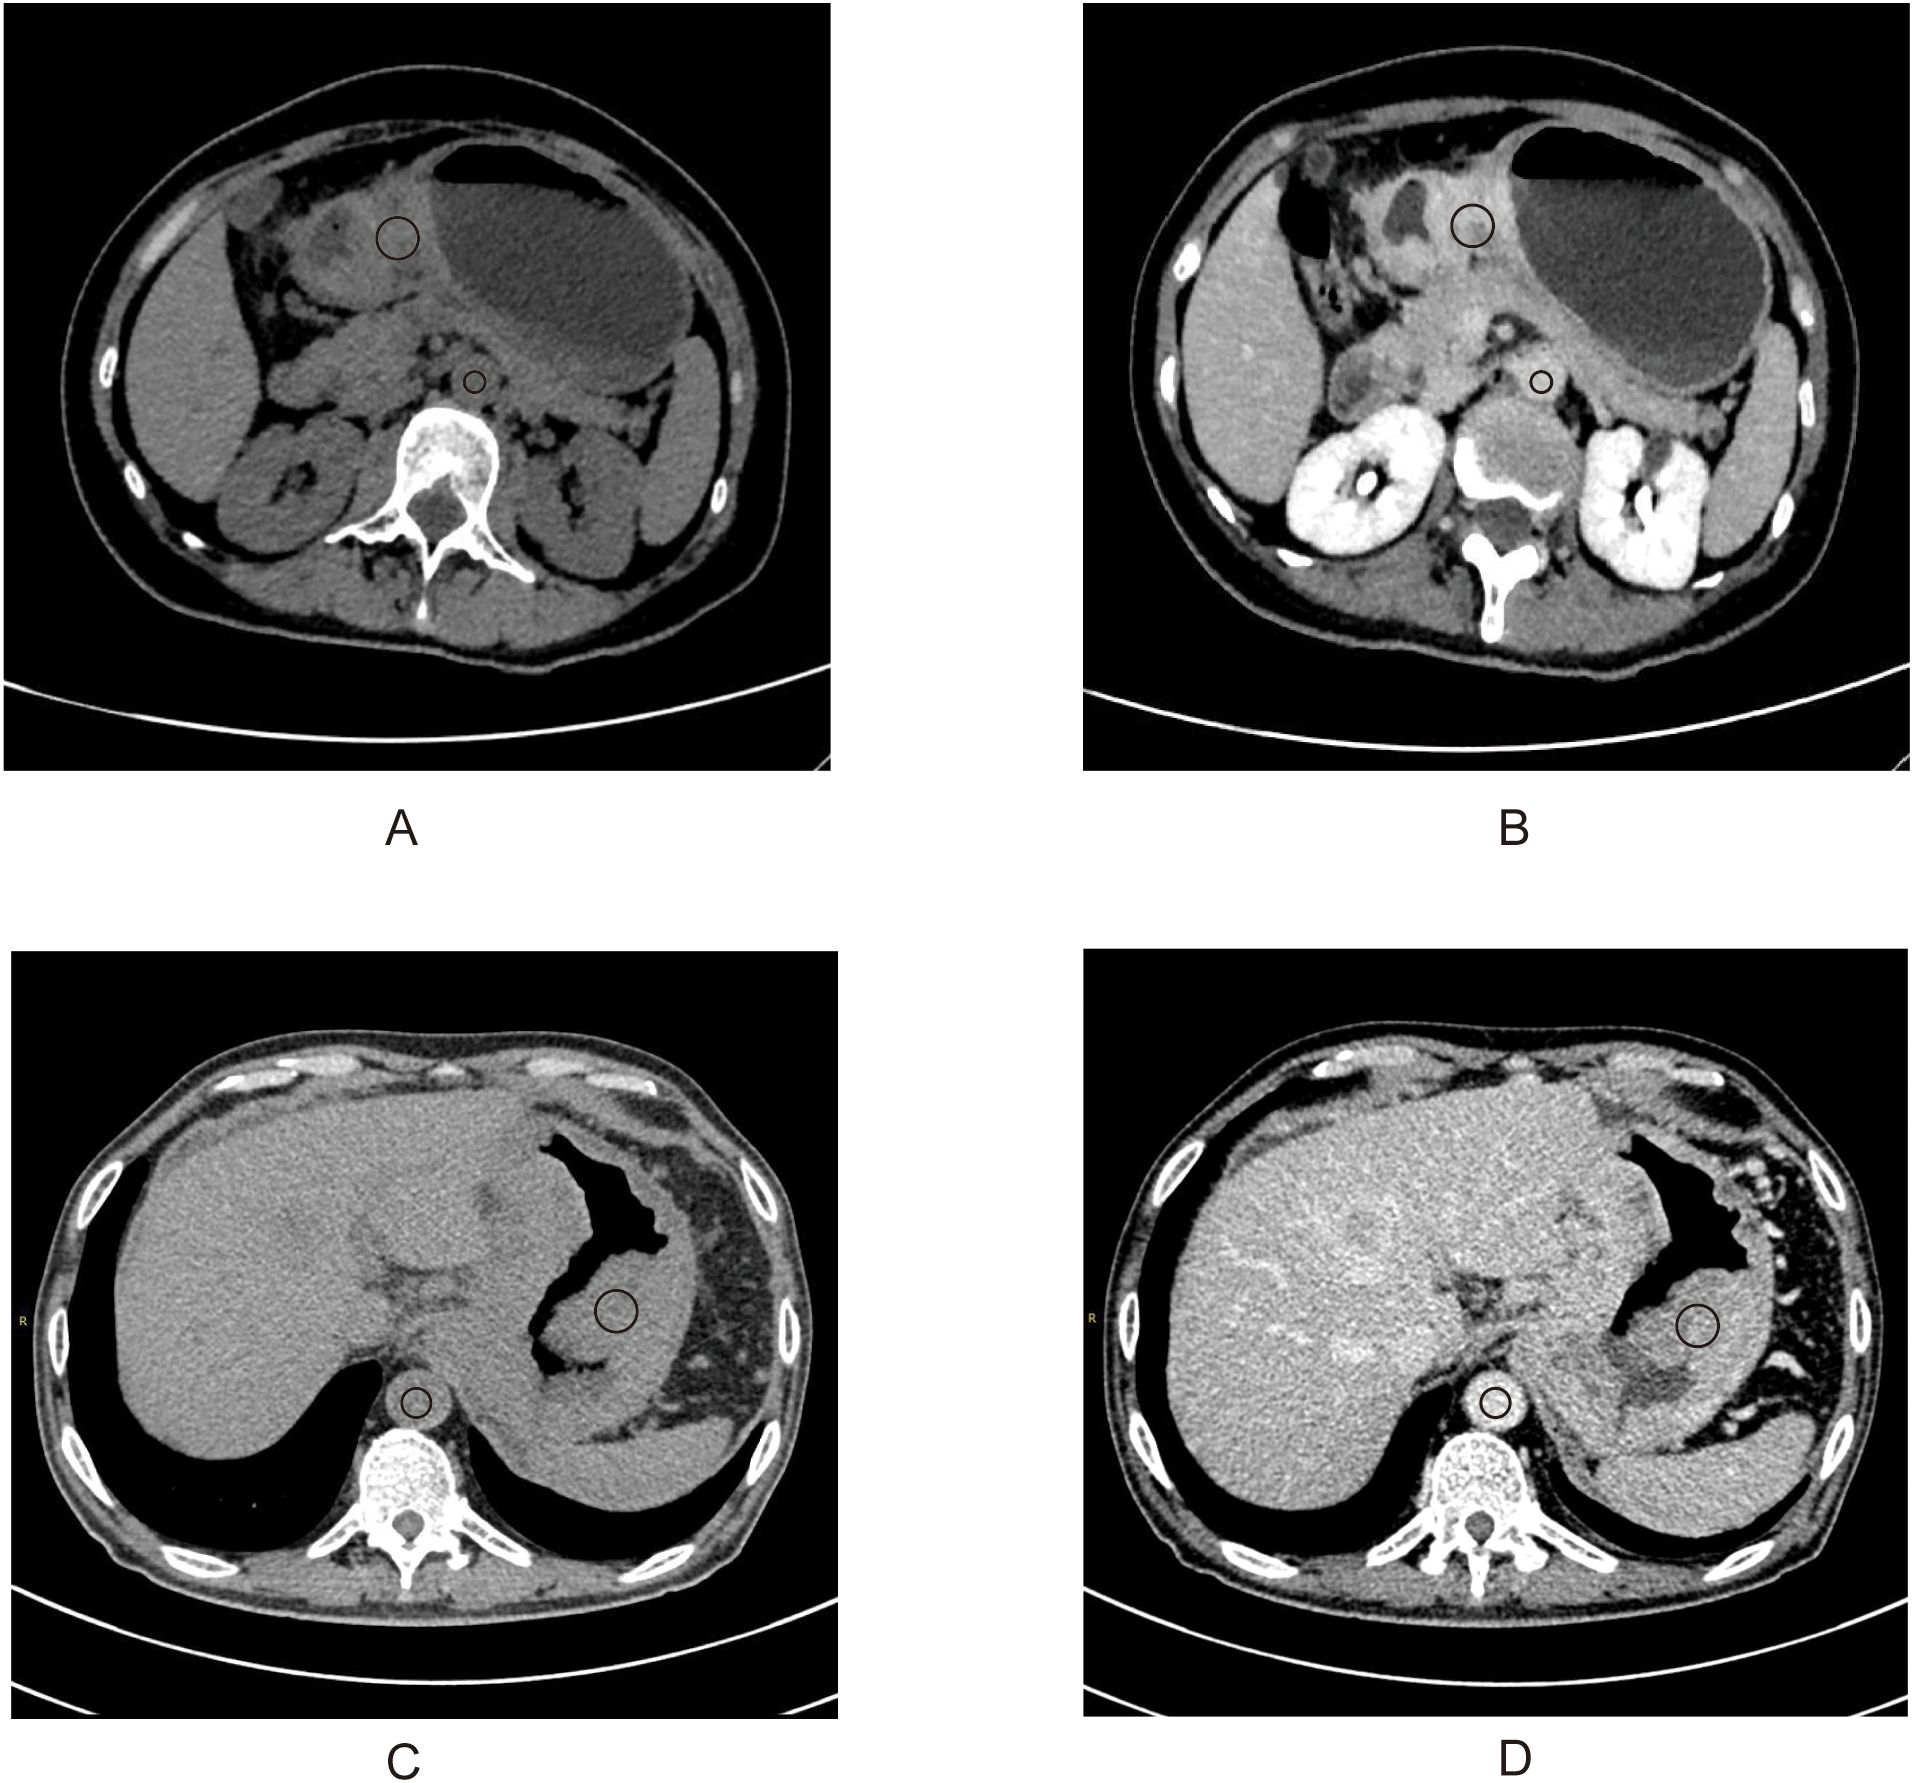

Prediction of Long-term Survival in Gastric Cancer Patients after Immunotherapy Based on CT-derived Extracellular Volume Fraction

Background: Gastric cancer remains a leading cause of cancer-related mortality. While immune checkpoint inhibitors (ICIs) have emerged as promising therapies, their efficacy is hindered by the lack of robust patient-centric biomarkers. CT-derived extracellular volume fraction (ECV) has emerged as a novel approach for non-invasive quantification of the extracellular matrix (ECM). This study assesses the predictive value of ECV, a non-invasive imaging biomarker, in gastric cancer patients receiving programmed death receptor-1 (PD-1) inhibitors. Methods: A retrospective study was conducted on 101 gastric adenocarcinoma patients (stage III: n=47; stage IV: n=54) treated with PD-1 inhibitors at Wuhan Union Hospital from June 21, 2020 to January 3, 2024. Patients were stratified into high and low ECV groups using X-tile software. Survival outcomes were compared using Kaplan-Meier curves and log-rank tests. Cox regression analyses identified independent prognostic factors. Two predictive models were developed and evaluated via receiver operating characteristic (ROC) curves, area under the curve (AUC), with internal validation using 1000 bootstrap iterations. Results: KaplanāMeier survival curves indicated that the ECV-higher group had shorter progression-free survival (PFS) (P< 0.001) and overall survival (OS) (P< 0.001) than the ECV-lower group. Multivariate Cox regression analysis confirmed that high CT-ECV was independently associated with worse PFS and OS (PFS: HR = 2.716, 95% CI: 1.432 - 5.152, P = 0.002 and OS: HR = 2.593, 95% CI: 1.322 - 5.084, P = 0.006). Conclusion: CT-derived ECV may serve as an independent predictor of long-term survival in gastric cancer patients undergoing immunotherapy.